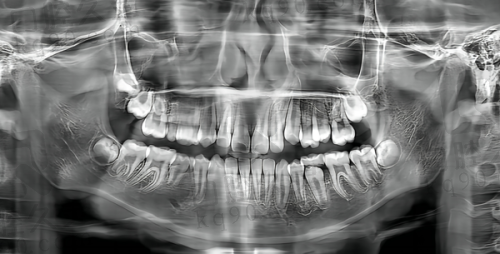

精良的设备对于口腔治疗来说非常关键。广州德伦口腔(东风总院)拥有一系列精良的口腔诊疗设备。这些设备能够帮助医生更正确地诊断口腔问题,制定更合适的治疗方案。比如在牙齿矫正方面,精良的设备可以严谨测量牙齿的位置和角度,让矫正成效更加理想;在种植牙手术中,设备能清晰显示口腔内部结构,提高手术的安心性和成功几率。精良的设备就像是医生的“得力助手”,为患者的口腔治疗提供了有力的支持。